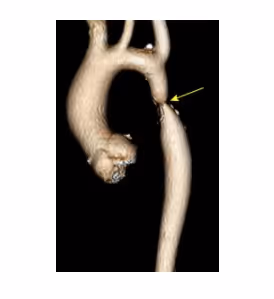

Patient with a Stanford type A aortic dissection

2021-03-08

in

Clinical Cases